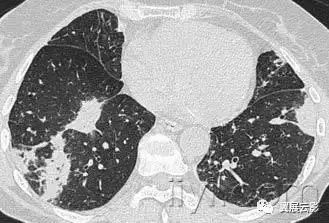

一、急性间质性肺炎

病理:不明原因的弥漫型肺泡病变。急性期特征为水肿和透明膜形成,晚期表现为含气腔隙和/或间质的机化。

病理上难以与急性呼吸窘迫综合征鉴别。平片和CT:急性期显示为双侧片状磨玻璃影,一些小叶可以不受累,产生地图样影像。在机化期,可以有结构的扭曲,牵拉性支扩,网状密度增高影。